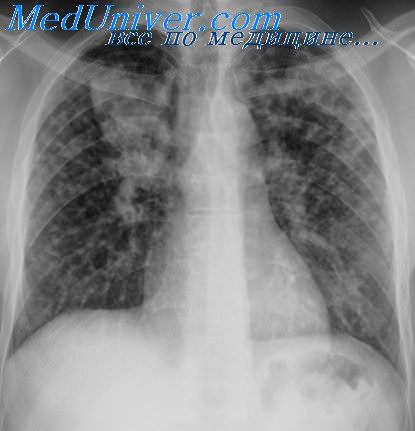

Часто операция проводится при обнаружении туберкуломы. Это воспаление, вызываемое палочкой Коха. Воспалительный процесс приводит к возникновению некротическо-казеозному образованию в тканях легкого. Туберкуломы выявляют с помощью рентгена грудной клетки и флюорографии. Но из-за схожести этих полостных образований с раковыми опухолями, их часто путают.

3. Рентген грудной клетки. С помощью исследования выявляют патологические очаги инфекции.